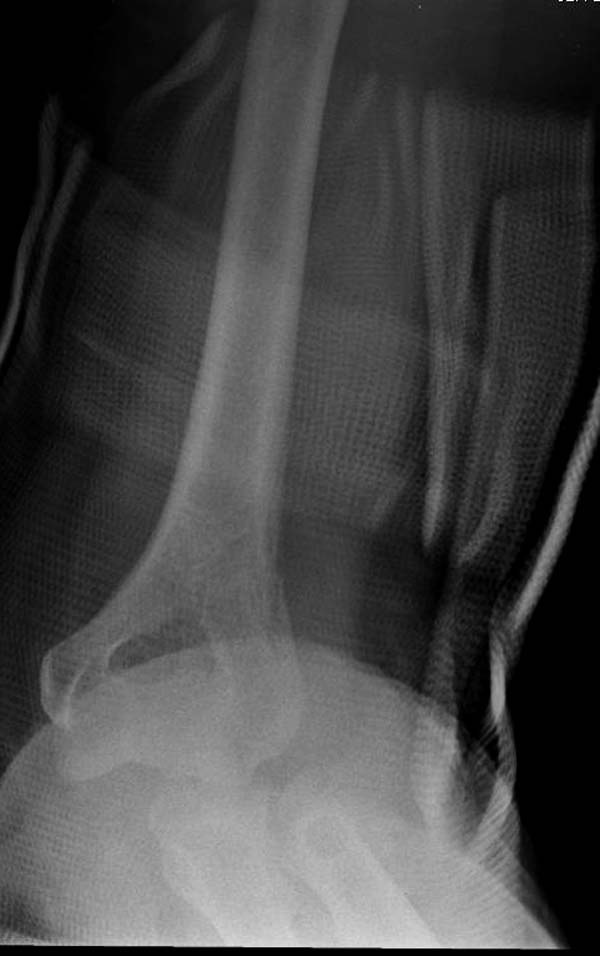

Снимки: 1-2 вывих, 4-5 вторичное смещение в гипсе, реконструкция

Имя     : 1 Elbow dislocation injury.jpg

Тип     : image/jpeg

Url     : http://weborto.net:8080/pipermail/ortho/attachments/20131212/4b05a6a3/attachment-0006.jpg